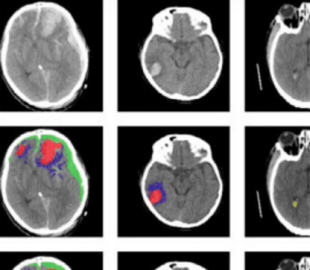

Новый инструмент ИИ автоматически определяет разные типы черепно-мозговых травм, анализируя результаты компьютерной томографии. Система использует алгоритм машинного обучения для выявления типов поражений мозга и областей тканей, поврежденных в результате травм или болезни.

Система основана на нейронной сети, разработанной исследователями Имперского колледжа Лондона. Ученые обучили инструмент на более чем 600 компьютерных снимках с различными типами поражений мозга. Они обнаружили, что ИИ успешно классифицировал отдельные части каждого изображения.